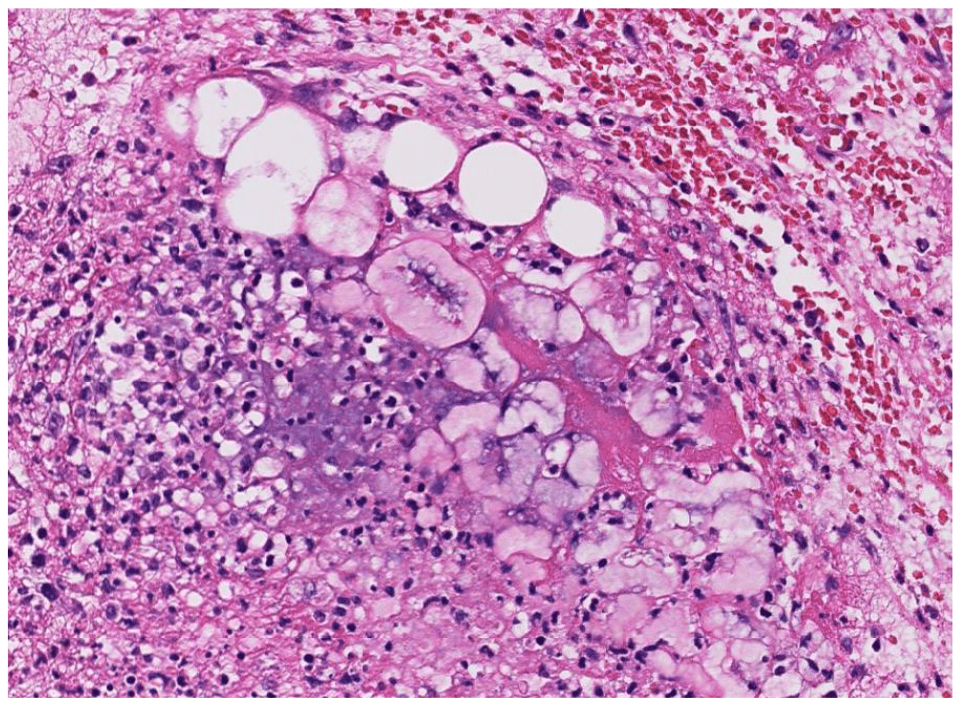

Pathology Lab 1

應該會考

2. epithelial infoldings and papilla

3. invaginated respiratory epithelium with cystic dilation